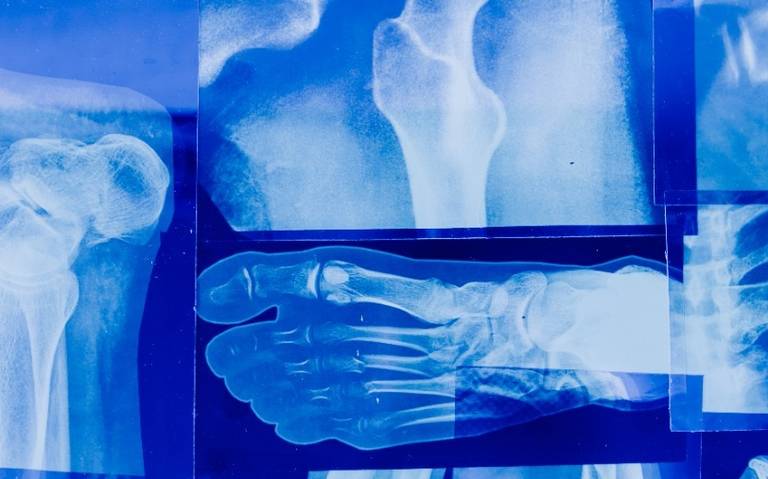

Seis de cada 10 personas tienen mala calidad ósea: IMSS Chihuahua

La mala calidad ósea aumenta la fragilidad, riesgo de fracturas y de osteoporosis

El encargado de la Jefatura de Prestaciones Médicas del IMSS en Chihuahua, doctor José Daniel Figueroa Alonzo, informó que 6 de cada 10 personas tienen mala calidad ósea, lo que aumenta la fragilidad y riesgo de fracturas, por lo que exhorta a llevar a cabo medidas preventivas para evitar osteoporosis y otras complicaciones. Sin embargo, afirmó que esta enfermedad se puede prevenir o bien se puede retrasar su aparición.

Añadió que la osteoporosis es una enfermedad crónica y progresiva que origina una disminución de la masa ósea, con el aumento de su fragilidad y fracturas.